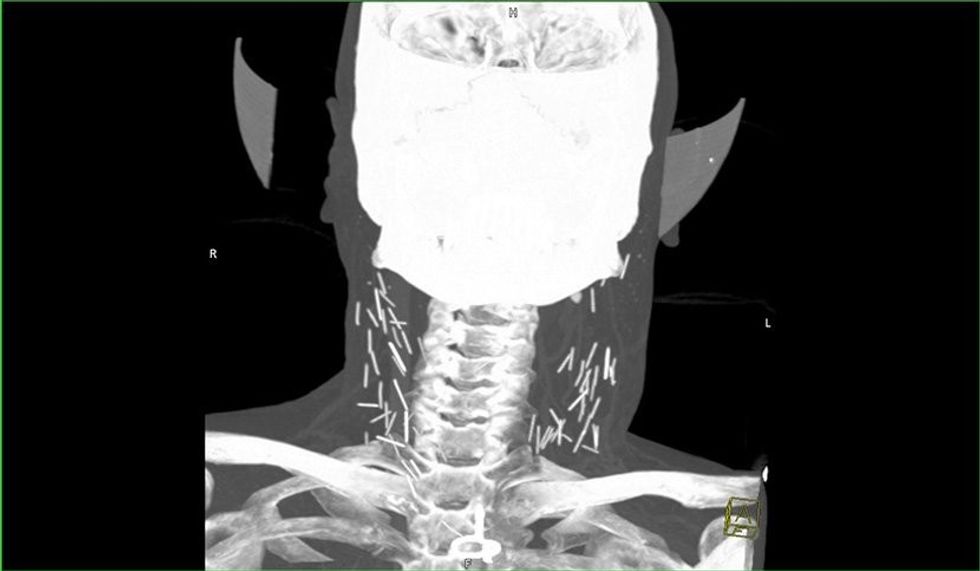

Fotografia e rëntgenit me rreze x ka nxjerr në pah dhjetëra gjilpëra të thyera në qafën e tij, ndërsa pas rekonstruimit të fotografisë në versionin 3D nga radiologët, është konstatuar se vërtetë bëhet fjalë për dhjetëra gjilpëra.

Mjekët besojnë se ky narkoman i cili sipas të gjitha gjasave nuk kishte pasur ku të shpohet në duar, dhe kështu kishte injektuar heroinën në venat e qafës.

Injektimi i heroinës në qafë mund ta lë pavetëdije narkomanin për disa sekonda, ku si pasojë gjilpëra mund të thyhet dhe një pjesë e saj të mbetet në qafën e tij.